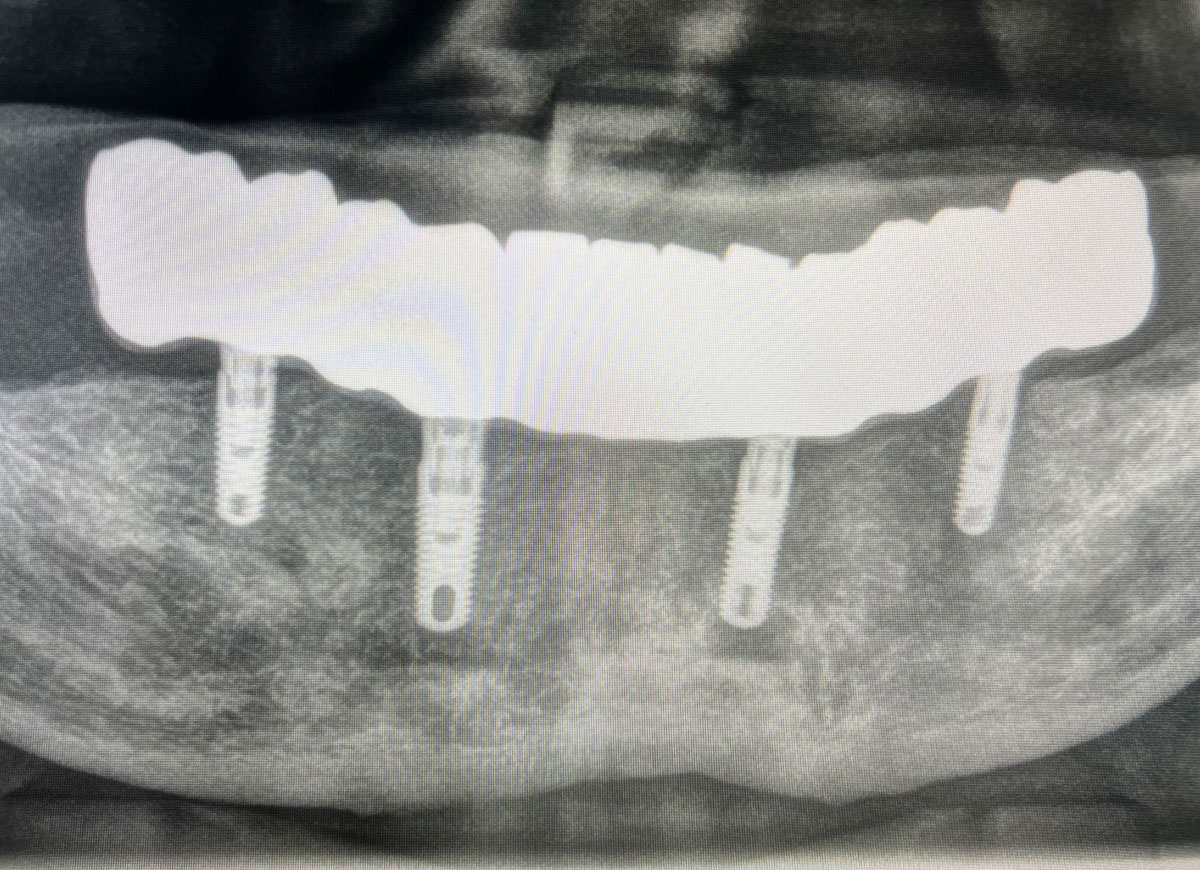

Protesi completa

su impianti all on six e all on four

Il dottor Filippo Marianelli e la sua equipe eseguono interventi di implantologia di alto livello grazie ad una tecnica all’avanguardia come la “All on Six” e la “All on Four”.

La tecnica si avvale di 4 o 6 impianti dentali inseriti nell’arcata superiore o inferiore che fungono da sostegno ad una protesi fissa.

L’implantologia All on Six e All on Four nascono per ovviare alla scelta obbligata della dentiera e finalmente poter contare su denti fissi, che garantiscano stabilità e comfort a lungo nel tempo. Durante questo intervento, lo specialista avviterà le protesi direttamente sugli impianti osteointegrati, inseriti sull’osso residuo.

Durante un primo incontro, il dottor Filippo Marianelli valuterà la situazione e la migliore soluzione possibile basandosi su un’accurata analisi del caso clinico e su uno studio della TAC

(Cone Beam).

La parte diagnostica radiografica pre-chirurgica è fondamentale e nel nostro studio, con appositi software, si riescono a programmare prima le dinamiche dell’intervento riducendone l’invasività.